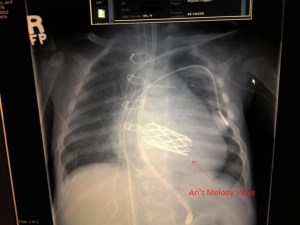

Worth noting, they interviewed me before I had the mitral valve replacement. Which, if you haven’t seen, is wild.

[…] images and told her he doesn’t believe it’s cardiac related. You’ve all seen pictures of his new mitral valve. It’s big and weird and wacky, so it doesn’t read like native valve on echo. And, again, it was […]